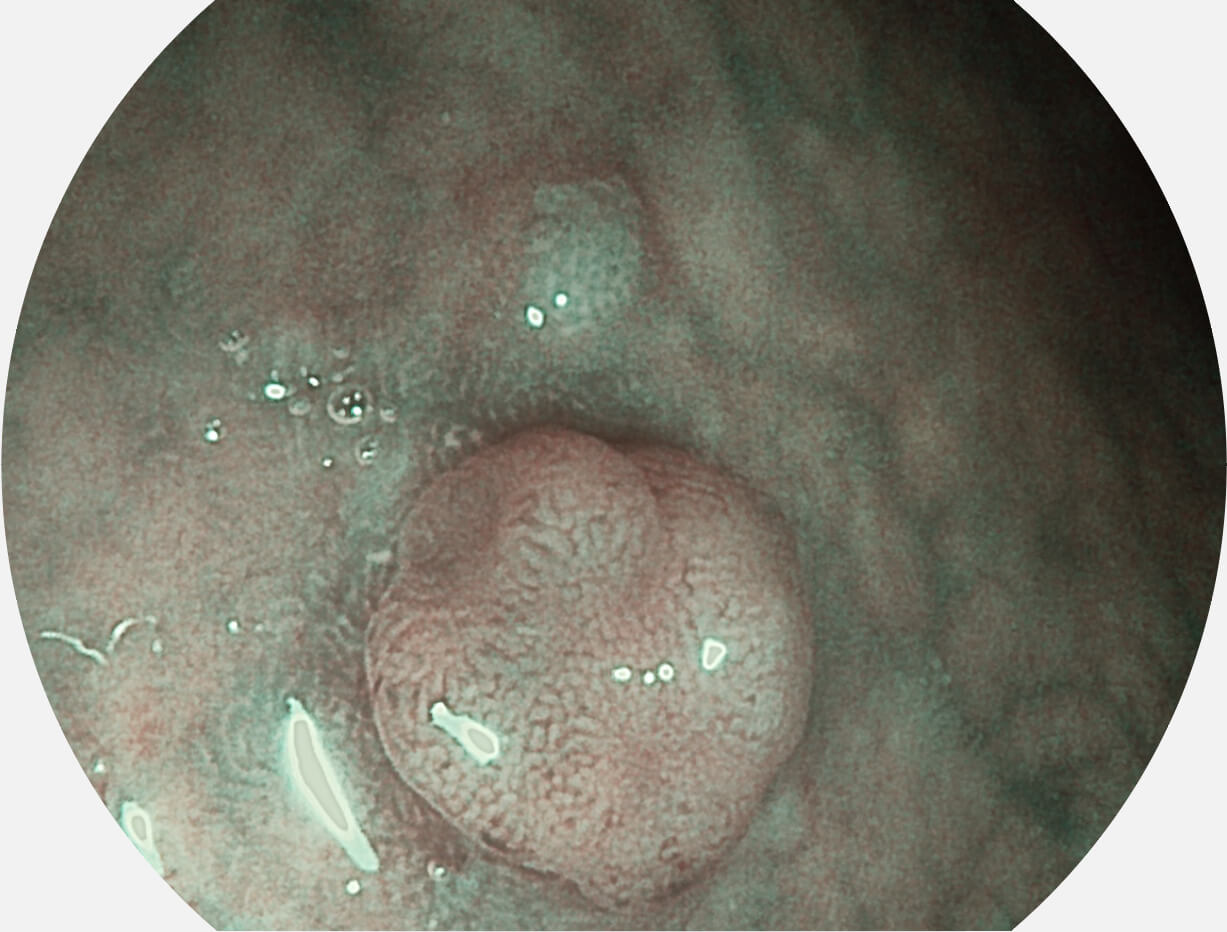

聚谱成像技术

Spectral Focused lmaging, SFI

图像具有高亮度、高黏膜血管颜色对比度的特点,且不改变粘液、食物残渣、粪便的基本颜色,可在中远景下进行观察,助力消化道早期疾病的诊断。

• 白光图像 SFI图像